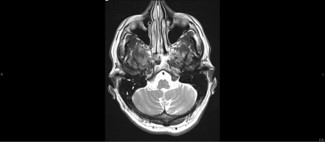

An accompanying 3T MRI showed contrast enhancement in the right facial nerve with mastoid effusion, a condition associated with COVID-19 [4,5]. Effusions on the mastoid of COVID-19 patients, thickening of the facial nerve, and subarachnoid space closure on the facial nerve were noted (Figures 2, 3 & 4). He was started on ivermectin 13 mg for 10 days and subsequently every month. His diplopia resolved within a month, and his feet felt warmer.

Figure 2: Axial Flair image demonstrates focal lacunar ischemic lesions in right frontal lobe (arrows).

Figure 3: Axial T2 weighted image demonstrates multiple scattered foci of fluid signal (arrows) suggestive of mild right mastoid effusion.